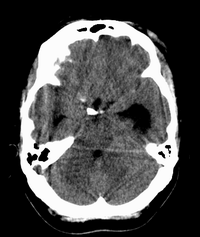

患者,女性,33岁,外伤检查发现,既往没有明显类似病史。

左侧脑室内软组织肿物,内部见多发不规则钙化,边界清楚锐利,有分叶。相应左侧脑室扩张。常见的不外乎3种病:室管膜瘤,脑膜瘤,脉络脉丛乳头状瘤。脑膜瘤分叶较少见,脉络脉丛乳头状瘤钙化较少见,因此,室管膜瘤可能性最大。

1室管膜瘤(肿瘤以膨胀性生长,有包膜,与周围分界清晰,大多位于脑室内ct表现为等密度,稍高密度肿快,边缘不光整呈分爷状。瘤内常见小圆状,块状钙化影。)2脑室内脑膜瘤(多位于侧脑室三角区ct平扫表现稍高于脑组织的肿快,无明显钙化。好发成年女性。)3脉络丛乳头状瘤(易引起交通性脑积水,颅高压症状明显)。总和以上考虑室管膜瘤可能性大。

左侧脑室内见不规则略高密度团块影,边缘分叶,内见多发不规则钙化,病灶与侧脑室壁关系较为密切,左侧脑室扩大。考虑室管膜瘤可能性较大,其次为脑膜瘤,脉络丛乳头状瘤的可能性最小。

患者,女性,33岁,外伤检查发现,既往没有明显类似病史;

1、病灶除钙化外其它部分质均匀,无明显密度差别;

2、病灶界清,呈现膨胀性生长,对周围组织无明显浸润表现;

3、钙化部分范围较大,呈现大片状钙化;

4、病人为成年女性,无明显不适;

考虑:脑膜瘤;

鉴别诊断:室管膜瘤;脉络膜乳头状瘤;